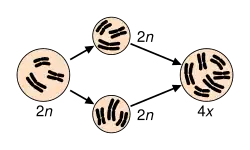

Maintaining a euploid state, where cells contain the correct number of chromosome sets, is essential for genomic stability. [5] Aneuploidy, characterized by an abnormal number of chromosomes, occurs when an individual is missing a chromosome from a pair (monosomy) or has an additional chromosome (trisomy). [6][7][8] This may be either full, involving a whole chromosome, or partial, where only part of a chromosome is missing or added.[6][7][8] Aneuploidy may arise from meiosis segregation errors such as nondisjunction, premature disjunction, or anaphase lag during meiosis I or II. [9] For aneuploidy, nondisjunction, the most frequent error, particularly in oocyte formation, occurs when replicated chromosomes fail to separate properly, leading to germ cells with an extra or missing chromosome.[9] Additionally, polyploidy occurs when cells contain more than two sets of chromosomes. [10] Polyploidy encompasses various forms, including triploid (three sets of chromosomes) and tetraploid (four sets of chromosomes). [5] Tetraploidy often arises from developmental errors during mitosis, such as cytokinesis failure, endoreplication, mitotic slippage, and cell fusion. These errors can subsequently lead to aneuploidy. [5]